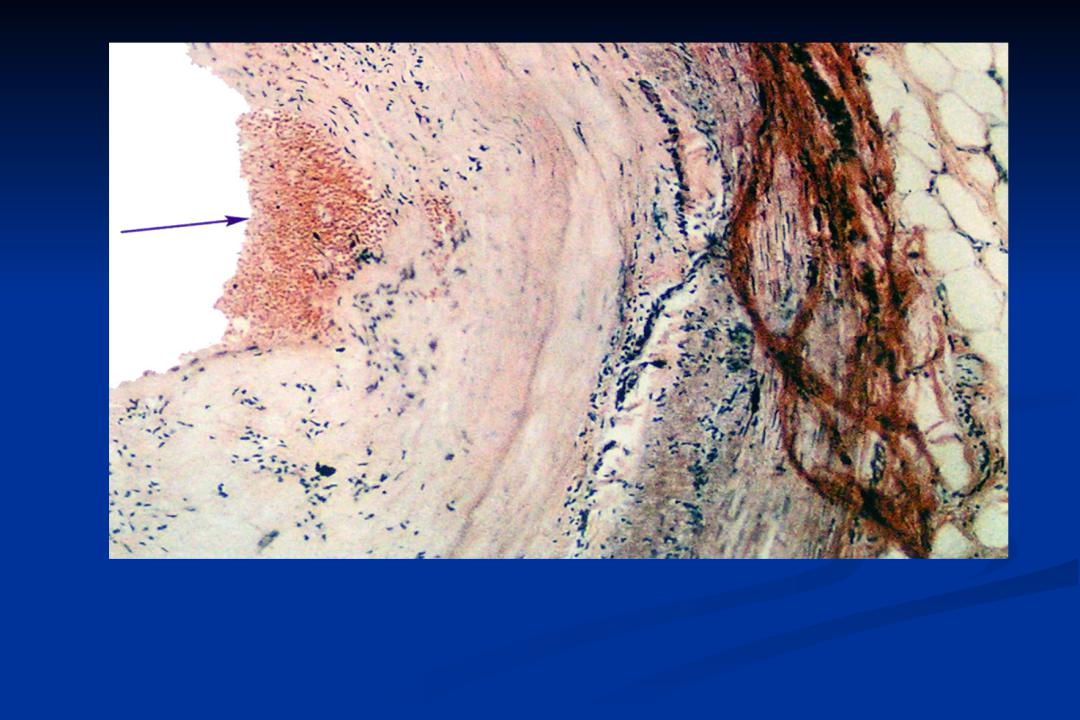

Образовавшийся тромб не остается в сосуде постоянно. Под влиянием естественных механизмов тромботические массы с течением времени могут рассасываться. В этом случае просвет вены и кровоток по ней восстанавливаются. Наступает реканализация тромба. Если рассасывание происходит не полностью, то часть тромботических масс организуется и превращается в фиброзную ткань, напоминающую рубец. Просвет вены в этом случае остается сужен в большей или меньшей степени или полностью закрыт (окклюзия).

В любом случае 100% восстановления вены не происходит. Венозная стенка после перенесенного тромбоза остается измененной, разрушаются клапаны, находящиеся в сосуде. Все это приводит к хроническим нарушения кровотока, получившим название посттромботической болезни.